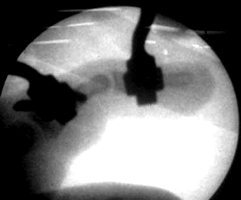

Endgliedtrümmerfraktur des Daumens - Ergebnis nach geschlossener Reposition

Trümmerfraktur des Daumenendgliedes. Alleiniger Zug am Finger ohne Eröffnung der Haut ermöglichen die gelenküberbrückende Stabilisierung mit einem Minifixateur.